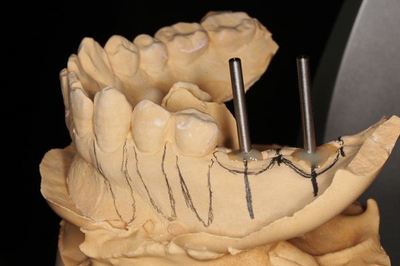

KaVo プロターevo7 咬合器に上下の歯列模型をマウントします。

CTデータと重ね合わせて、埋入位置・方向を決めます。

サージカルステント(ドリルガイド・ドリルスリーブ)を作製し

事前のシミュレーションを生かすように準備します。

すべてを私が行っています。